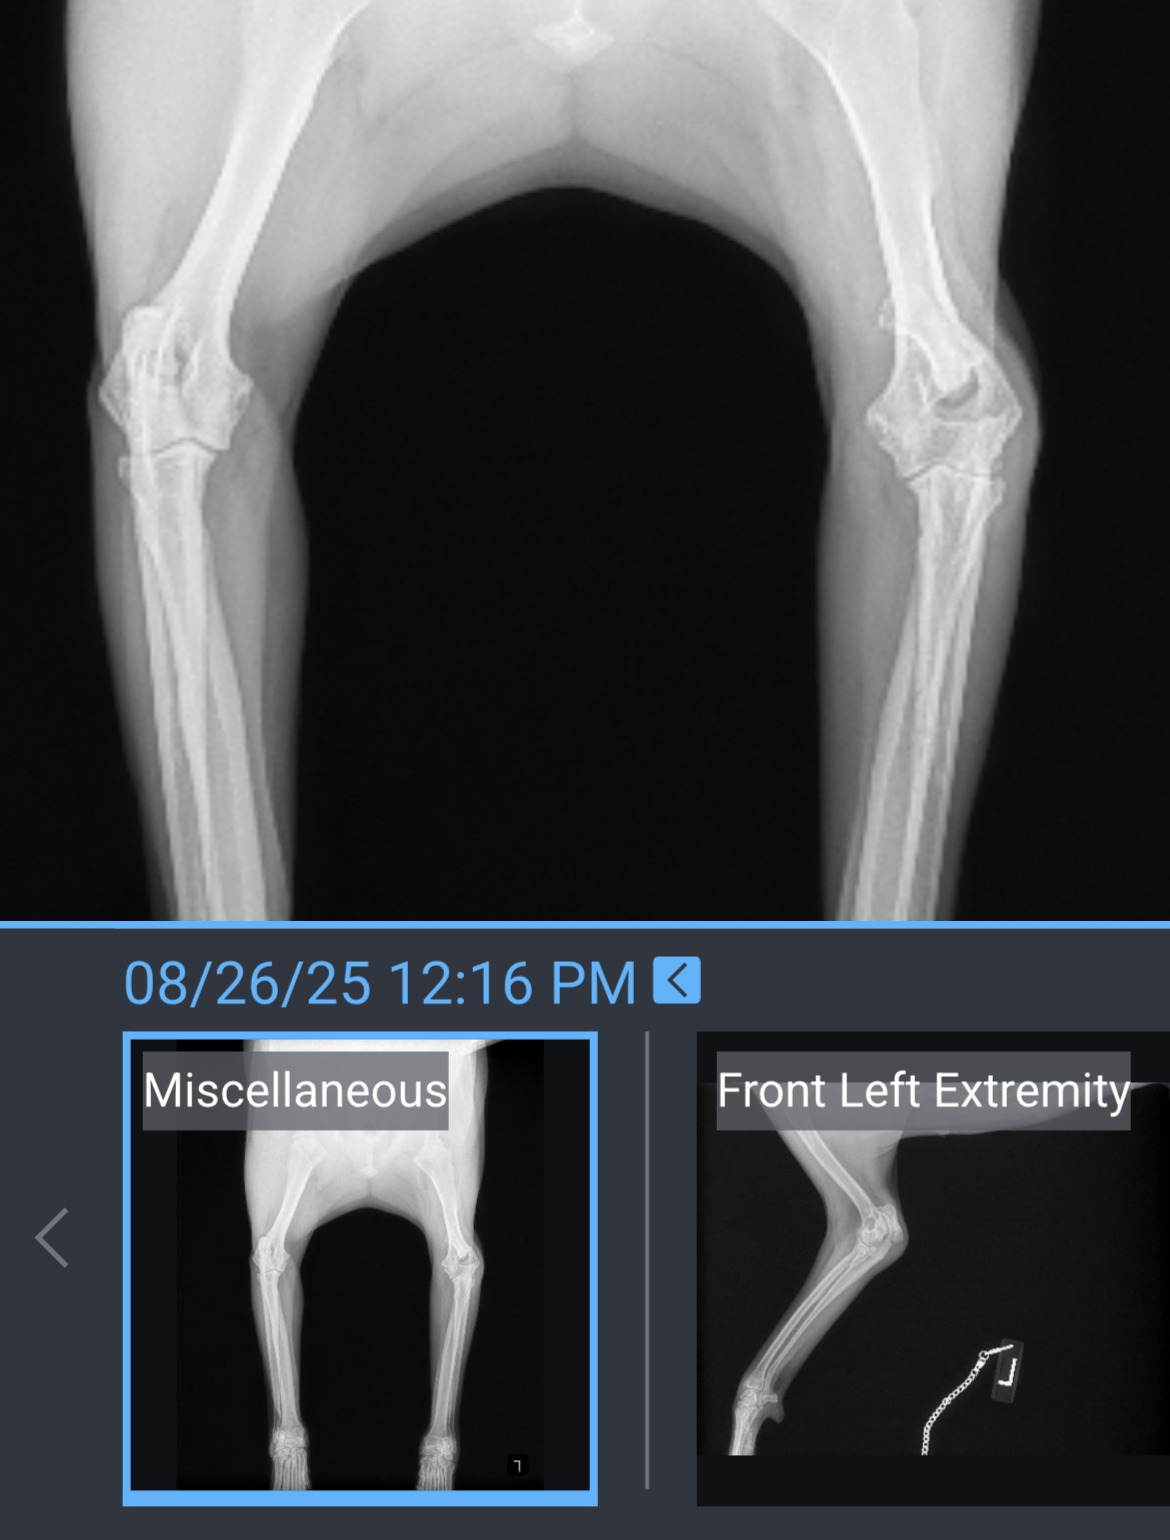

Sugar #A2698354 has been through more than any dog should ever have to endure. She arrived at the shelter on June 6, 2025 with a painful coronoid fracture in her elbow, leaving her unable to walk or bear any weight on her left front leg. While in the shelter’s care, she was also spayed while pregnant, a heartbreaking ordeal for any animal.

Since then, Sugar has been evaluated by two independent veterinarians, both of whom believe her leg can be saved with surgery.Now, we need your help to make that possible.

Sugar’s leg can be saved but time is critical. With your support, we can cover the cost of her surgery and give her the chance to live a full, pain-free life on all fours.